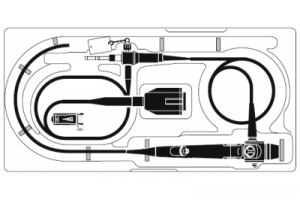

Портативный фиберскоп для трахеальной интубации LF-DP Olympus

- Портативный фиберскоп для трахеальной интубации LF-DP